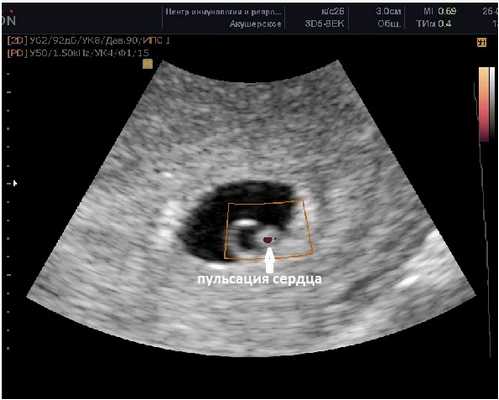

Внутри плодного яйца мы видим "колечко с драгоценным камнем" :) - это желточный мешок и уже хорошо различимый эмбрион, расположенные рядом. Сердце эмбриона начинает биться в начале 6-й акушерской недели беременности. Именно наличие пульсации сердца является достоверным ультразвуковым признаком прогрессирующей беременности. При КТР ≥6 мм и отсутствии пульсации сердца делается заключение об остановке развития данного эмбриона. Нормальная частота сердечных сокращений (ЧСС) эмбриона в самом начале 6-й недели 70-90 ударов в минуту, но уже к концу недели становится более 100 уд. в мин. На ранних сроках беременности большее значение имеет не ЧСС, а как таковое наличие или отсутствие сердечных сокращений. Иногда, при неразвивающейся беременности можно увидеть отражение пульсации сосудов матери внутри эмбриона и принять их за сердцебиение ребёнка. Но в этом случае частота пульсации будет идентична ЧСС матери.